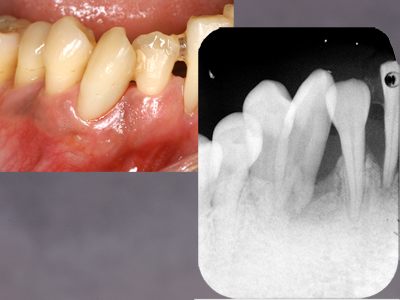

咬合性外傷

左上犬歯近心の骨欠損です。

EPT+.プラークコントロールが非常に良い方で赤染めではほとんどどこも染まりません。

ブラキシズムによる外傷と診断し、スケーリング、ルートプレーニングは一切せずナイトガードと自己暗示療法による外傷のコントロールを試みました。

初診と3ヶ月後の比較です。骨が少しずつ戻ってきました。